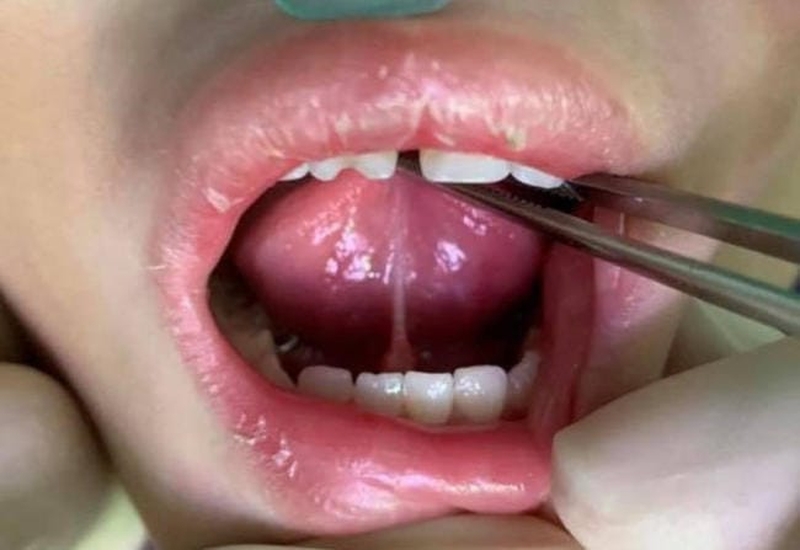

Dính thắng lưỡi độ 4 là mức độ nghiêm trọng nhất của tật dính thắng lưỡi ở trẻ sơ sinh. Vậy phải làm thế nào khi con yêu vừa vào đời đã mắc phải dị tật này? Bài viết hôm nay, chúng ta cùng tìm hiểu sâu hơn về bệnh trạng này nhé!

Thắng lưỡi hay phanh lưỡi ở trẻ nhỏ là một màng lớp niêm mạc hình tam giác nối giữa sàn miệng với mặt dưới của lưỡi. Khi phát hiện con bị mắc tật dính thắng lưỡi độ 4, rất nhiều ba mẹ không khỏi hoang mang, lo lắng. Thấu hiểu được nỗi lòng đó, trong bài viết này, chúng tôi sẽ cung cấp thêm cho các bạn những thông tin bổ ích cũng như phương pháp điều trị loại dị tật trên.

Các bác sĩ thường phân ra 4 cấp độ dính thắng lưỡi ở trẻ với những đặc điểm sau đây:

Có tới 4 mức độ của bệnh dính thắng lưỡi ở trẻ, trong đó dính thắng lưỡi độ 4 là nguy hiểm nhất

Theo các chuyên gia, khi trẻ sơ sinh bị tật dính thắng lưỡi sẽ phụ thuộc vào dây thắng lưỡi bị dính ít hay nhiều và mức độ ảnh hưởng đến cử động lưỡi, bú sữa mẹ, quá trình phát âm của trẻ mà đưa ra phương pháp điều trị khác nhau. Trường hợp trẻ bị dính thắng lưỡi độ 4 thì cần phẫu thuật cắt dây thắng lưỡi ngay, để tránh những hệ lụy về sau. Thông thường, bệnh nhi có dị tật dính thắng lưỡi sẽ được điều trị theo những bước sau:

Bệnh dính thắng lưỡi độ 4 ở trẻ cần được phẫu thuật càng sớm càng tốt